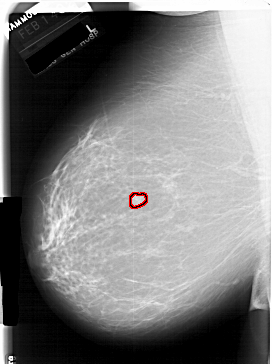

FILE: A_1940_1.LEFT_CC.OVERLAY

TOTAL_ABNORMALITIES 1

ABNORMALITY 1

LESION_TYPE MASS SHAPE LOBULATED MARGINS CIRCUMSCRIBED

ASSESSMENT 3

SUBTLETY 4

PATHOLOGY BENIGN

TOTAL_OUTLINES 1

BOUNDARY